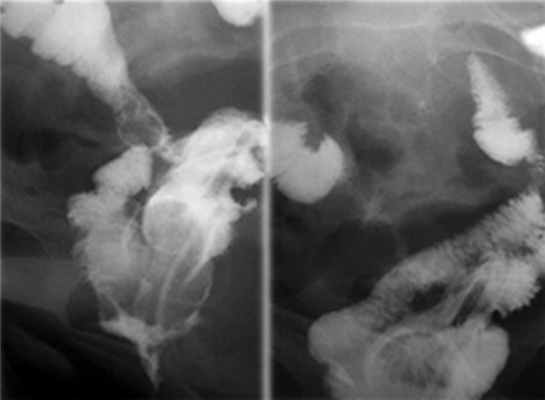

В послеоперационном периоде через 1 мес после операции состояние пациентки удовлетворительное, подтекания мочи не определяется. На контрольной цистограмме рефлюкса мочи нет (рис. 7). Больная удерживает мочу при помощи акушерского пессария (рис. 8, на цв. вклейке).

Рис. 7. Контрольные цистограммы через 1 мес после операции. Мочевой пузырь приобретает овальную форму. Рефлюкс мочи не определяется.